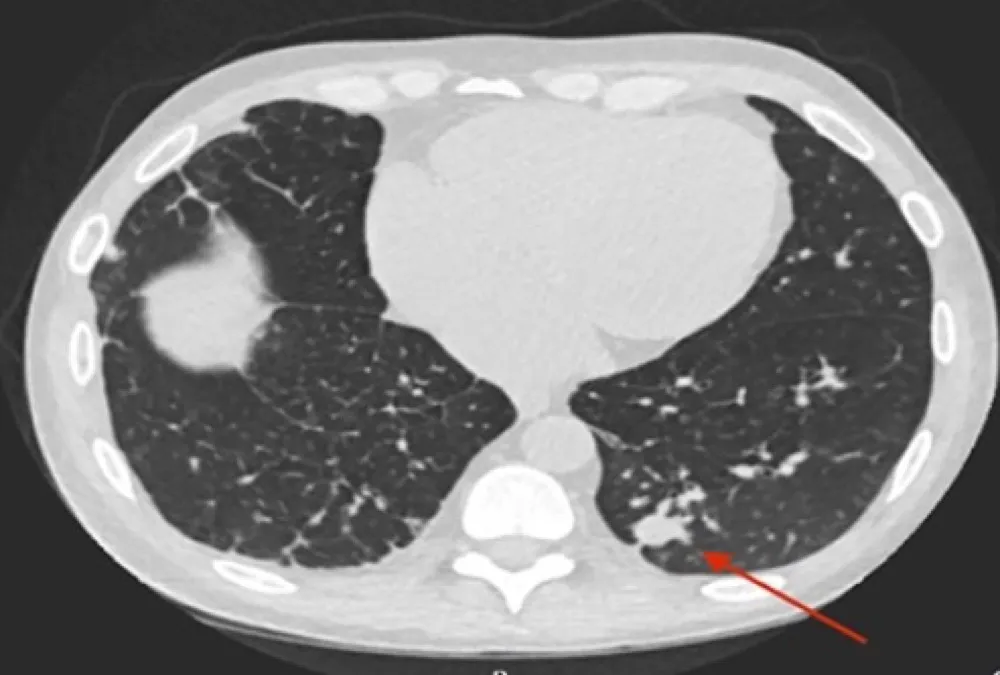

Uma causa incomum de hematúria glomerular intermitente!

Hematúria pós infecção, caso clínicos para auxiliar no entendimento de causas glomerulares comuns e raras...